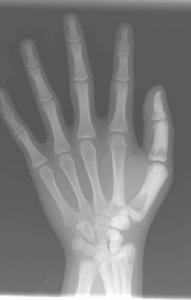

本病突出的x線改變為廣泛性骨硬化,骨呈無結構的密度增高,骨小梁影像消失,可累及全身或大部骨骼。其易發部位為脊柱、骨盆、肋骨、顱骨、脛腓骨及手足的短管狀骨。患者骨密度顯著增加,皮質增厚,髓腔變窄甚至閉塞。病變呈對稱性分布,小兒期即可顯示病變,重者未出生前子宮內即可發現。

(4)長骨:病變起始於乾骺端,漸向骨幹發展。常可見到深淺交替的波浪狀橫紋。同樣病變也可見於掌、跖、指、趾諸骨,在靠近骨骺一端較為明顯。

X線表現:基本X線表現廣泛均勻,骨密度增高硬化,骨小梁變粗、模糊,皮質增厚,髓腔狹窄,甚至消失。本院曾有3例石骨症病人,因發生骨折,欲行帶鎖髓內針固定,因髓腔消失,骨質硬化,改用鋼板或動力髁鋼板固定,骨密度增高有明顯的均勻對稱性,以四肢、肋骨和骨盆較明顯。骨中骨主要見於掌指、跖趾關節及肋骨等,骨中骨表現為邊界比較明顯的緻密骨島。夾心椎又名夾心蛋糕征,其形成是由於椎體上下軟骨板富含血管,在鈣吸收不足的情況,該部類骨質沉積過多。類骨質對破骨細胞具有明顯的抑制作用,而椎體中部缺乏這種類骨質,故而被破骨細胞侵蝕,形成椎上下高密度而中間低密度,形如三明治樣。髂骨翼年輪樣改變。射線可透過帶是較正常骨區域,而緻密帶存在大量不起作用的破骨細胞。顱骨穹窿顱底均增厚硬化,以顱底骨質增生最明顯。

本病X線表現具有特徵性,其特徵為骨骼濃厚緻密,失去其原有結構,無法區分皮質及髓腔,兩端膨大呈杵狀。有的患嬰在子宮內已有如此表現。全身大多數骨均可累及,但下頜骨少見。由於骨硬化過程可以變緩或暫停,因此,在骨骼上可見到有深淺不同的橫紋。骨骺亦緻密,有時可見呈同心圓狀。椎體的上、下兩端緻密,但中間有一條骨質正常的帶,常被形容為“夾心麵包椎體”。顱骨亦硬化,氣竇消失,垂體窩變淺,鞍背突增生,顱窩變狹,顱孔縮小。

石骨症為全身性骨骼受累的疾病,顱骨的X線表現為硬化,尤以顱底為顯著,特別是蝶骨體及大、小翼均明顯改變。蝶鞍大小正常或縮小,床突、鞍底皆硬化。顳骨及枕骨也可硬化,使板障封閉,失去三層的分野。頂骨額骨及顏面骨可不受侵犯或僅有輕微變化。視神經孔變窄且邊緣模糊乳突小房及鼻旁竇變小或發育不全石骨症在長管狀骨及脊椎有特徵性的X線改變。脊椎椎體表現為上下緣特别致密,其間密度低者為正常骨質,組成三層帶狀影。長管狀骨表現為“骨內骨”,骨質緻密髓腔變窄或消失於乾骺部顯示多條互為平行或呈波狀緻密線紋,乾骺部可呈杵狀變形,尤其脛骨上端內側可表現為邊緣不整呈粗鋸齒改變,髂骨翼典型改變為平行髂嵴,的多層的同心弧狀硬化帶此外,肋骨和鎖骨均可呈均勻硬化。有時還可見到骨折,於掌、蹠、指及趾骨常有界限分明的骨島出現。